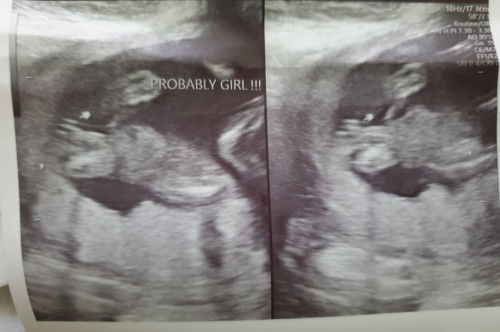

Sa tingin niyo po ba girl talaga to?

Ask lang po kung may chance to maging boy? Girl po panganay ko.